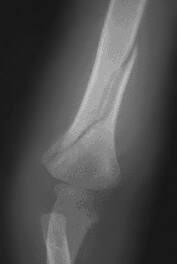

Spiral Fracture of the Humerus

Source: "AbuseWatch.net, n.d."

Seven-year-old Nick comes to the emergency room with an injured arm. His mother says he fell off the trampoline when he was jumping around and playing with his friend. An X-ray is ordered to assess for any breaks. When Nick’s arm is X-rayed, a spiral fracture of his humerus is identified.

Case Study 4

What indicators are present? Spiral fracture, the explanation for the injury is not plausible.

Is there reasonable cause to suspect abuse or maltreatment? Yes

Is there a parent or other person responsible for the suspected abuse or maltreatment? Mother

What are your next steps? Call SCR.